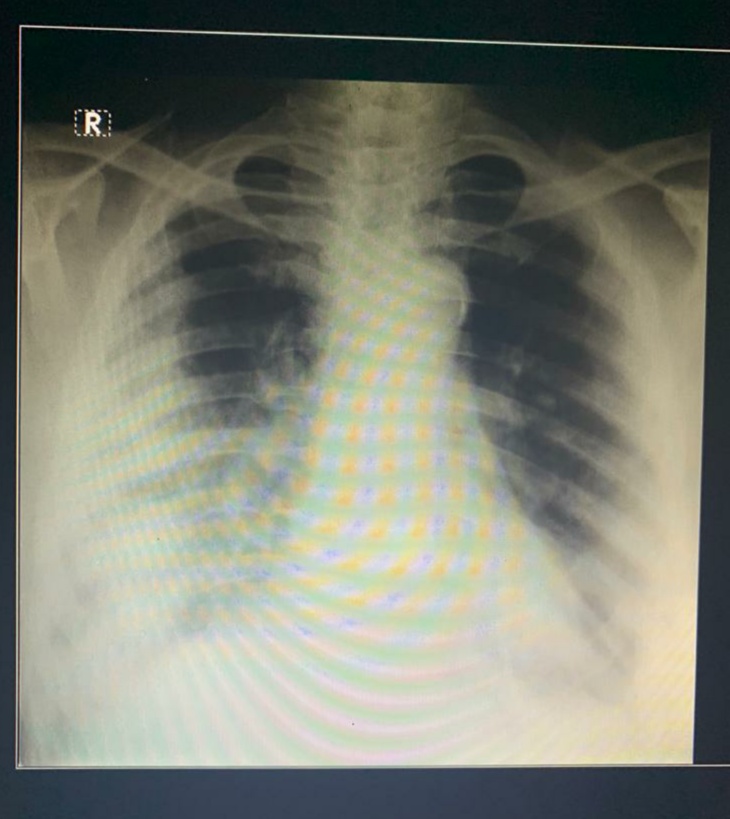

आजची एका मित्राची ओपीडी

74 वर्षे male

एक्स रे वर R मार्क असतो , ती पेशंटची उजवी बाजू असते

पिवळ्या रंगाचे डॉट डॉट आहेत

पिवळ्या रंगाचे डॉट डॉट आहेत ते काय आहे

ते डॉट नाहीत , डिजिटल एक्स रे

ते डॉट नाहीत , डिजिटल एक्स रे आहे , त्याचा मोबाइलवर फ़ोटो घेताना ते कयामेरा आर्टिफेक्ट आले आहेत

हा करोना बाधा झालेल्या

हा करोना बाधा झालेल्या व्यक्तीचा xray आहे का?म्हणजे एरवी नॉर्मल फुफ्फुस भरीव आणि करोना झाल्यावर वरच्या भागात दिसते तसे रिकामे होते का(हा प्रश्न कोणी यामागे अड्रेस केला असे तर माफी.)

Lung apices क्लिअर आहेत?